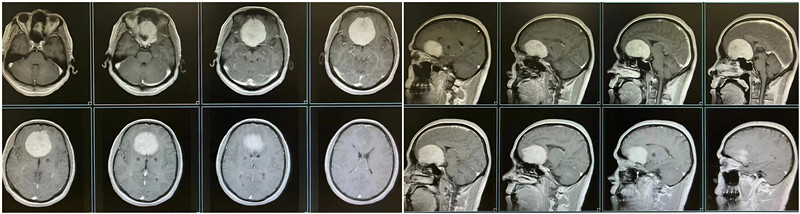

2023年3月初,彭先生开始频繁出现头晕头痛、视力模糊、嗅觉减退等症状,于外院行头颅CT检查提示:前颅窝巨大占位。2023年3月25日,彭先生来到我院神经外科进一步就诊。神经外科李松年主任医师接诊后,迅速为彭先生完善核磁共振等相关检查。结果显示:彭先生颅内存在直径达70mm占位病变。考虑前颅底嗅沟巨大脑膜瘤。

肿瘤血供及其丰富,颈内、颈外动脉同时供血。巨大的瘤体已引起神经功能损害,手术指征明确。由于肿瘤位置特殊,与周围许多重要结构关系密切,手术难度高。神经外科手术团队与国内神经外科顶尖专家进行多次讨论,制定了周密的手术计划及预后诊疗方案并与患者及患者家属充分沟通。

患者术前头颅MRI